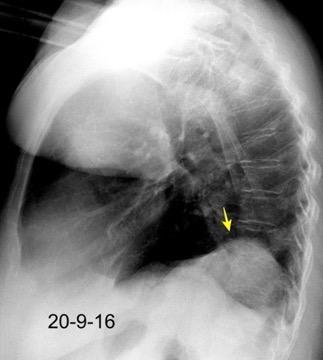

Parálisis frénica transitoria tras cirugía de válvula aórtica

Parálisis frénica transitoria post cirugía cardiaca (10%).

Puede acompañarse de atelectasia del LII.

Benjamin JJ et al. . Left lower lobe atelectasis and consolidation following cardiac surgery: the effect of topical cooling on the phrenic nerve. Radiology 1982